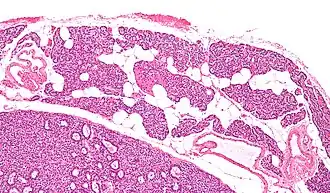

![]() Микропрепарат: Паращитовидная железа — слева внизу аденома паращитовидной железы. |